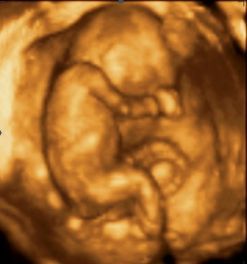

А зато сегодня было столько эмоций!!! Во-первых увидели малышика, а во-вторых та неуходящая амниотическая жидкость исчезла и желточный мешочек уже не визуализируется!!! Нам записали видео и фото! Пересмотрели все уже на 100 раз))) вот одна из фоточек:\

Вот такой у нас малыш)))

Малышь на фоточке просто чудесный, я тоже так хотела всего полностью заснят, но срок уже был большеват, и он совсем тогда в меня спрятался))) А у вас очень здорово получилось, растите и развивайтесь, здоровья вам с малышом)))

КРУТО:) нереально круто:) Я НЕ ЗНАЛА И ДАЖЕ НЕ ДУМАЛА,что на таком небольшом сроке- МАЛЫШИ ТАКИЕ КРАСИВЫЕ ...неописуемо...

Хоть срок еще совсем маленький, но врач с уверенностью более 50 % сказала, что будет девочка))) Ты прямо ясновидящая)))))))))))))))))))))) у нас на видео есть кадр, где она улыбается!!!